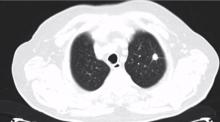

A 78-year-old patient was admitted to the authors' department for a left upper lobe nodule resection. The patient had a past history of smoking and comorbidities, including hypertension and COPD. He had no symptoms, but an x-ray revealed a nodule in the left upper lobe. The CT scan confirmed that there was an 11 mm nodule with a malignant appearance. Percutaneous transthoracic fine-needle aspiration revealed that the nodule was an adenocarcinoma. Bronchoscopy showed an endo-bronchial squamous carcinoma in the superior segment of the right lower lobe. The FEV1 was 1680 (76%) and the DLCO 92%.

Considering the nodule size and that the patient would need a further right resection, the authors planned a VATS trisegmentectomy, sparing the lingula, for the left nodule. A 3-4 cm utility incision was performed anteriorly in the 5th intercostal space. The thoracoscopic access was performed in the 8th intercostal space, on the posterior axillary line. An 11 mm nodule was detected in the left upper lobe and the lingula was not affected.